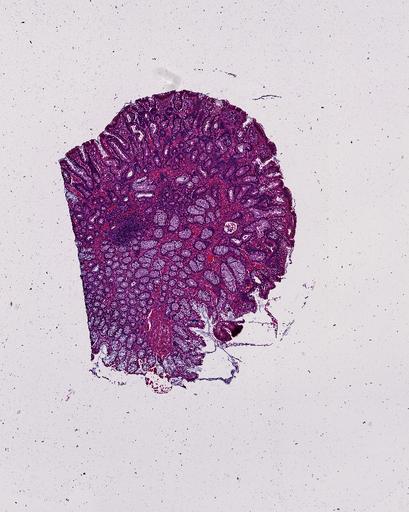

High‑resolution three‑dimensional (3D) tissue atlases promise to redefine how we study cellular architecture‑function relationships in human tissues. Large-scale consortia such as the Human Bimolecular Atlas Program (HuBMAP) systematically build detailed 3D organ maps by profiling serial tissue sections with single-cell spatial technologies. However, an accurate and efficient reconstruction method that can handle atlas-scale datasets remains elusive. We introduce Space-map, an open-source method that integrates single‑cell coordinates with optional histological image features to assemble serial sections into 3D models. Space‑map combines multi‑scale feature matching with large‑deformation diffeomorphic metric mapping, delivering global reconstructions while preserving local micro‑anatomy. To demonstrate the capability of Space-map, we generated a serially sectioned spatial transcriptomics (Xenium, ~2.9M cells) dataset and a spatial proteomics dataset (CODEX, ~2.4M cells). Applying Space-map to these single-cell spatial maps, we built three 3D models for both diseased (colon polyp) and reference colon tissues. These high-resolution 3D models showcase the intricate structure of the human colon across different states. Space-map is fast and highly efficient. We demonstrated its performance and accuracy using in‑house and public datasets. The result shows that Space‑map is 10 times faster and ~2‑fold more accurate than PASTE and STalign, making 3D atlas reconstruction more accessible. Our study provides a new robust and user-friendly software available at https://github.com/a12910/spacemap that can be easily applied for constructing molecular 3D tissue maps of human organs at single-cell resolution.